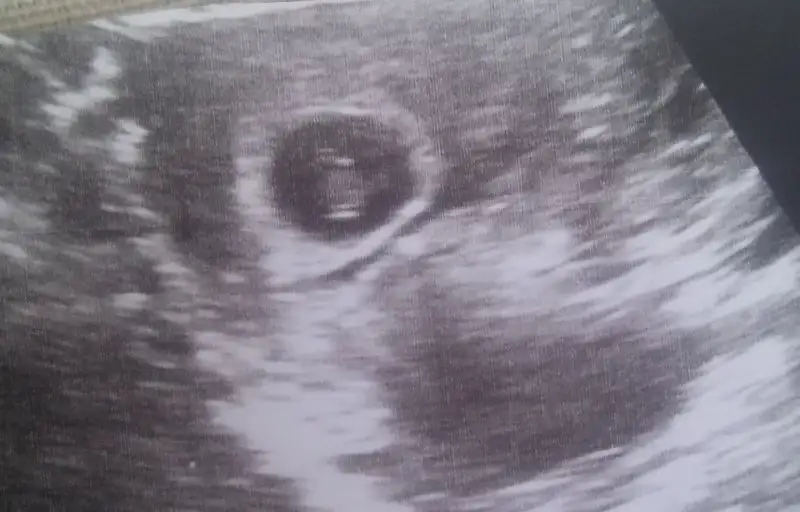

Vajinal ultrason 6 haftalık yorumlarmısınız?

• 4DFA11E2-0057-472C-9BD0-63C8C9B07A67.webp

8,3 KB · Görüntüleme: 170